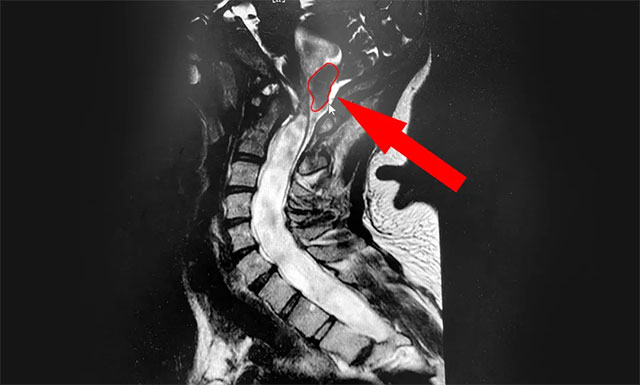

▲ MRI示患者小脑扁桃体下疝畸形

侯增欣主任耐心询问了患者病史,并开展了有针对性的检查。小潘的颈椎核磁检查报告很快出来了,从影像上看,患者的颈6/7椎间盘确实稍有突出,但程度并不严重。而导致患者症状不断加重的“元凶”同时现形:小脑扁桃体延长成楔形进入了枕骨大孔及颈椎管,颈髓受压水肿改变,颈髓及上端胸髓内见条状异常信号,提示为“Chiari畸形伴脊髓空洞症”。

侯主任解释道,Chiari畸形,又称为小脑扁桃体下疝畸形(Arnold-Chiari malformation,ACM),是因为后颅脑先天发育异常,小脑扁桃体向下延伸,压迫脑干、脊髓而引起的一种疾病,是引起脊髓空洞症的常见原因。这一类型的脊髓空洞症患者可出现枕部头痛(由咳嗽、喷嚏等引起)、颈肩部疼痛、小脑共济失调表现、头晕、声音嘶哑、吞咽困难、睡眠障碍等一系列症状。